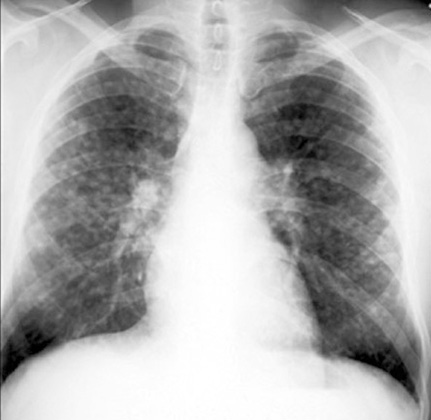

Sarcoidosis

Miliary Nodules